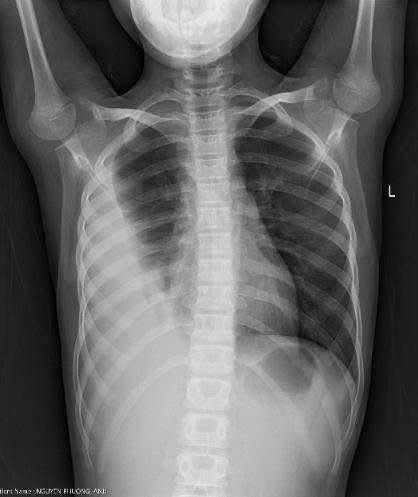

viem-mu-mang-phoi.jpg

Biểu hiện viêm mủ màng phổi trên phim chụp - Ảnh BVCC

Các bác sĩ khoa Nhi Ngoại tổng hợp – Bệnh viện Sản nhi tỉnh Ninh Bình cho biết, viêm mủ màng phổi là tình trạng nhiễm trùng nặng, gây tích tụ mủ trong khoang màng phổi, dầy dính màng phổi ảnh hưởng nghiêm trọng đến hệ hô hấp và sức khỏe của bệnh nhân. Việc điều trị viêm mủ màng phổi nếu không kịp thời và đúng cách có thể dẫn đến nhiều biến chứng nguy hiểm.